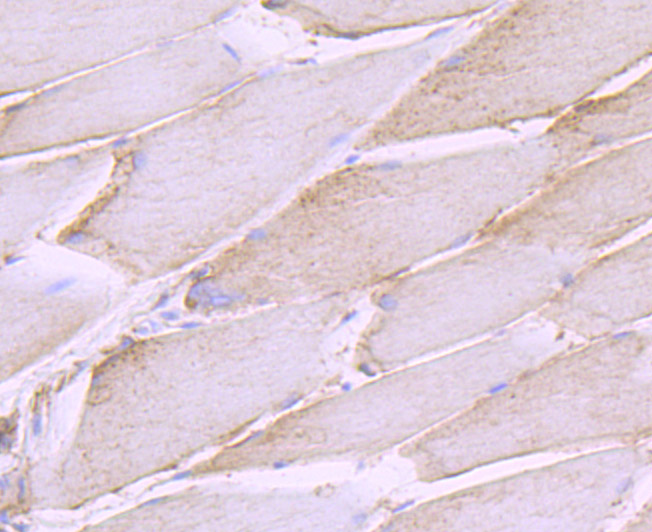

Immunohistochemical analysis of paraffin-embedded rat skeletal muscle tissue using anti-SHP2 antibody. Counter stained with hematoxylin.